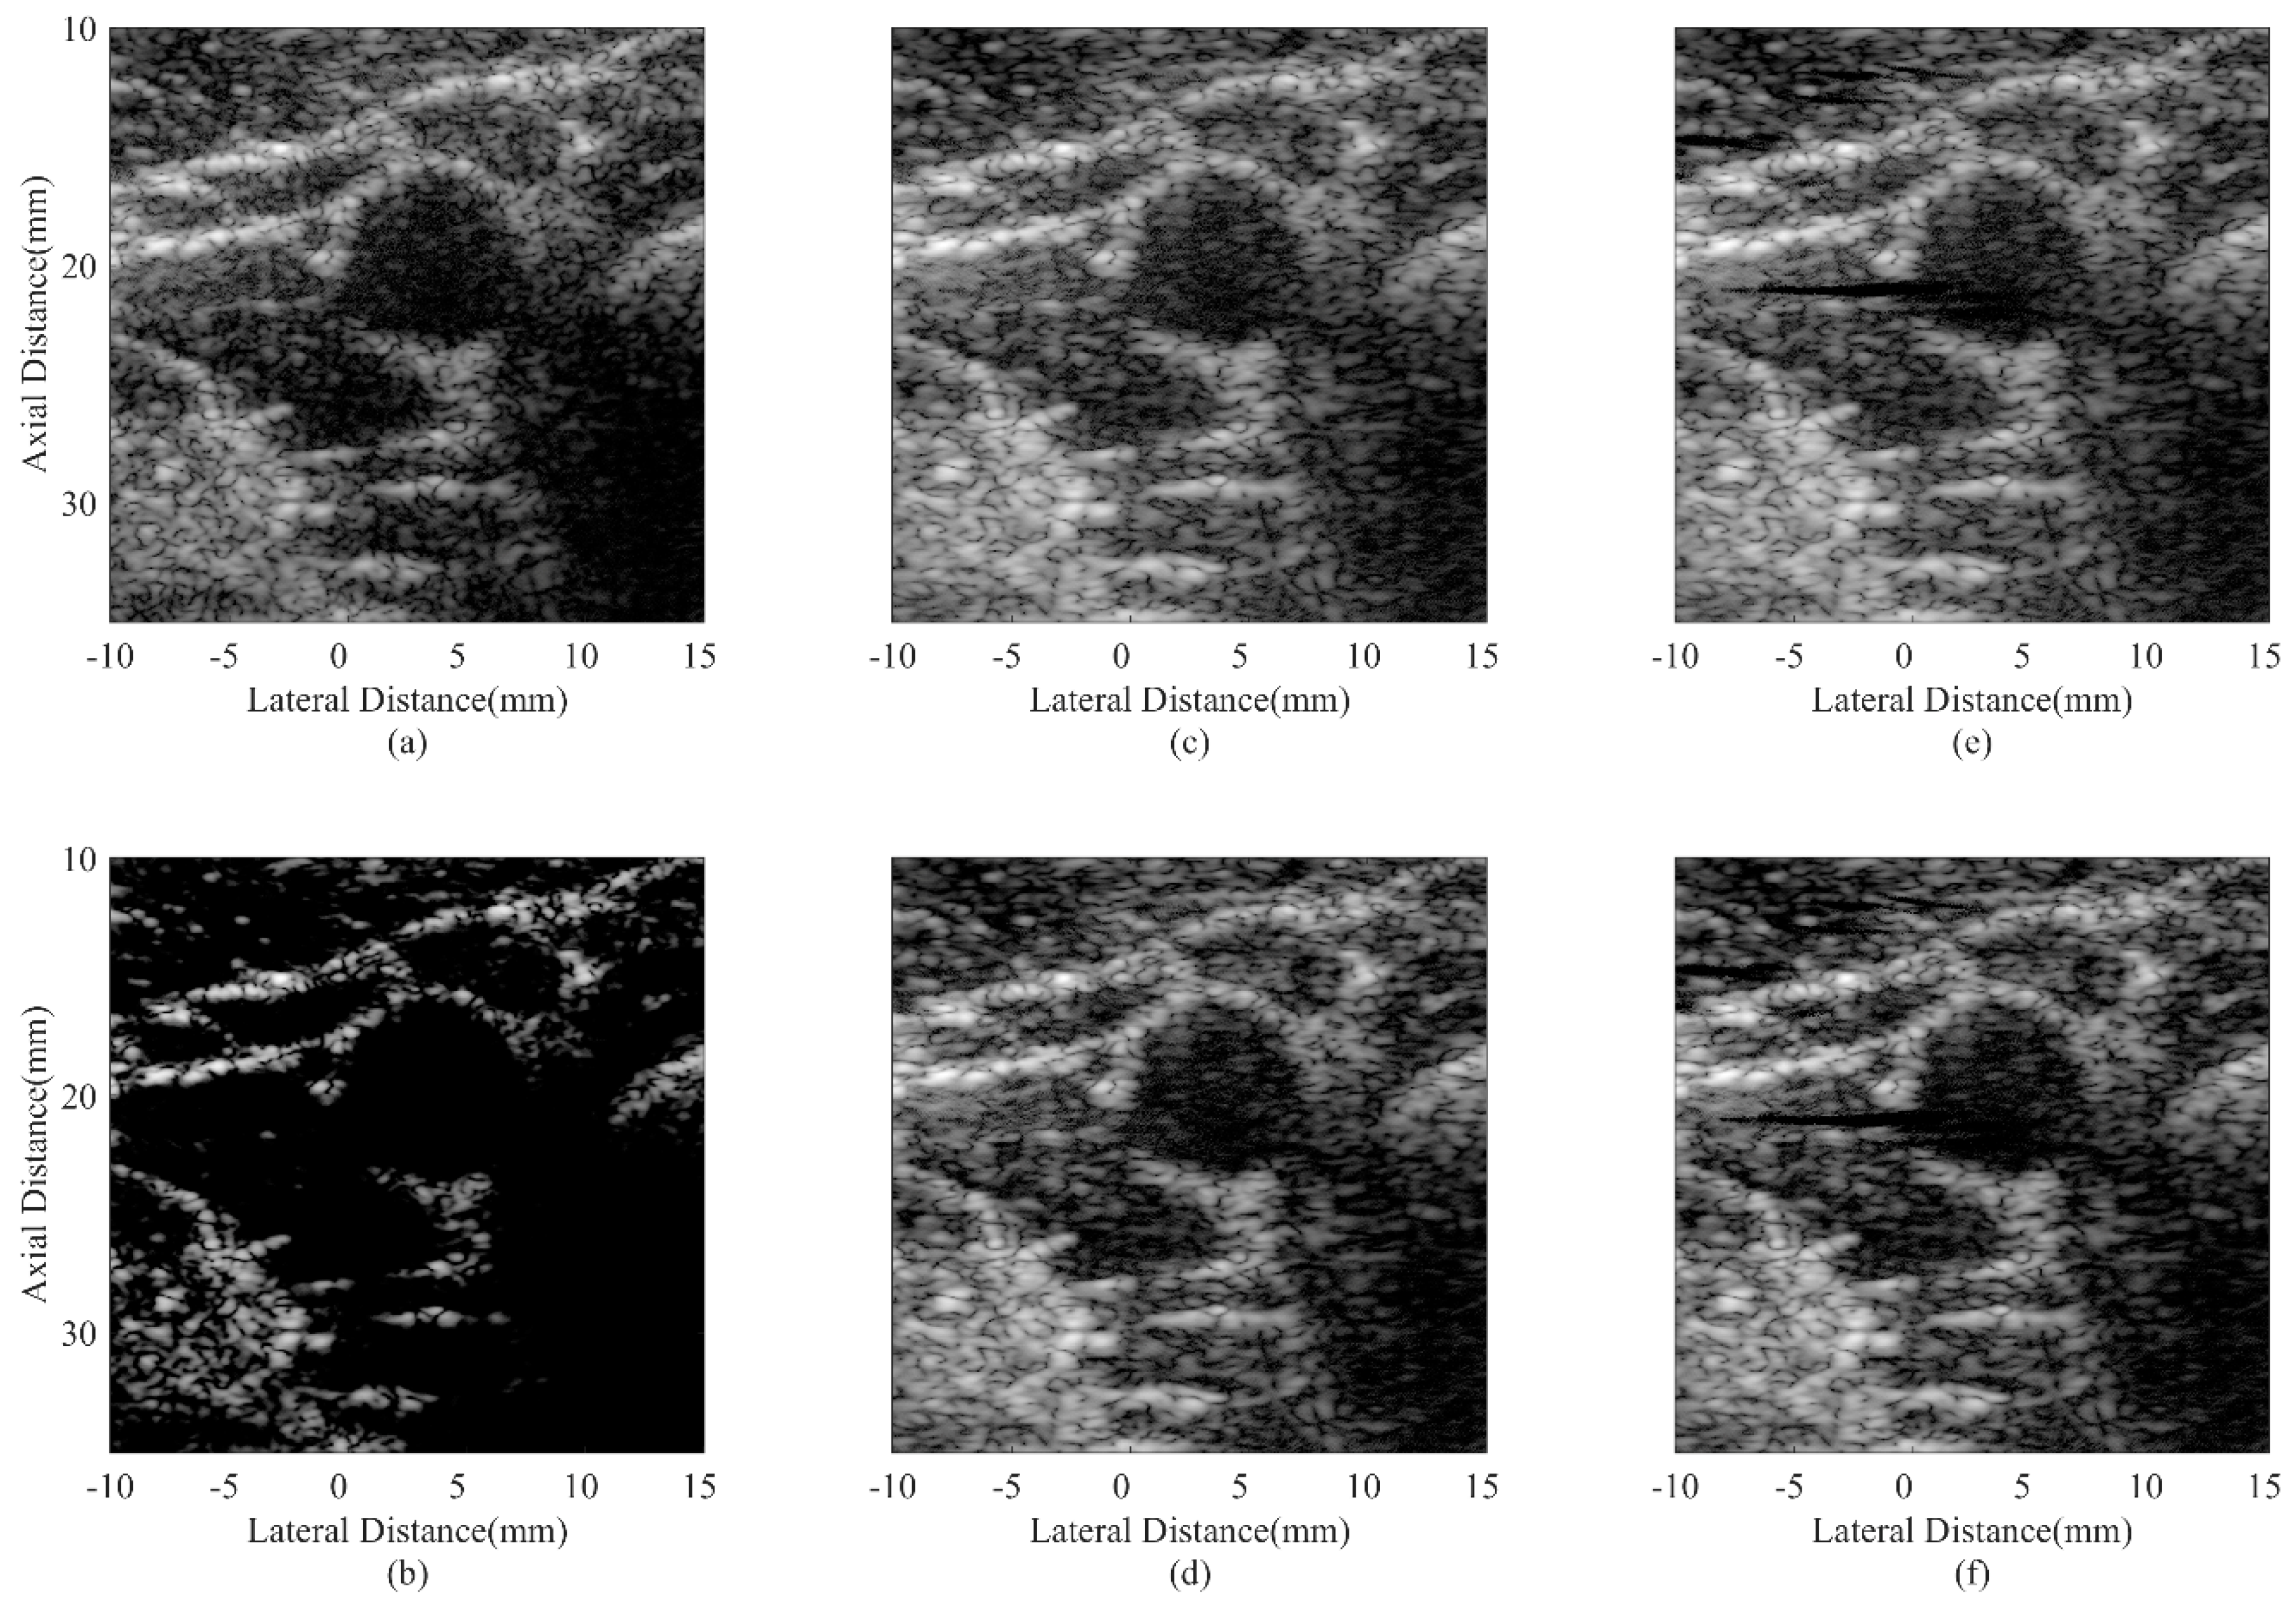

| Beamformer | CR (dB) | CNR |

|---|---|---|

| DAS | 30.32 | 1.76 |

| CF JTR-MV JTR-MV GCF JTR-ESBMV JTR-ESBMV GCF | 76.77 29.87 33.27 50.97 64.01 | 1.13 1.82 1.74 1.86 1.78 |